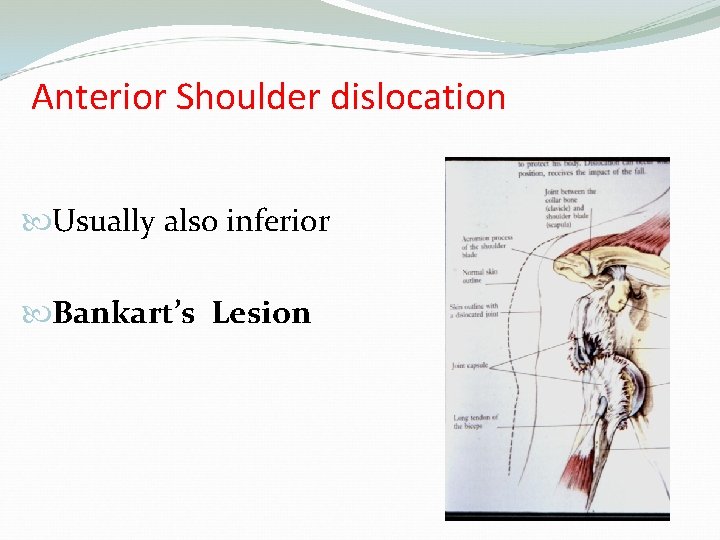

Anterior Shoulder dislocation Usually also inferior Bankart’s Lesion